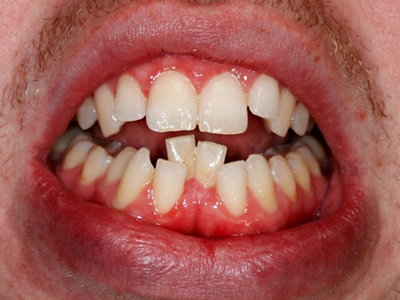

阻生牙是指由于邻牙、骨或软组织的阻碍而只能部分萌出或完全不能萌出,且以后也不能萌出的牙。引起牙阻生的成因,主要是由于颌骨缺乏足够的空间容纳全部恒牙。常见的阻生牙为下颌第三磨牙、上颌第三磨牙及上颌尖牙。

阻生牙可反复引起冠周炎,或引起邻牙牙根吸收和破坏,位置不正,不能完全萌出,好发部位是上、下颌第三磨牙。